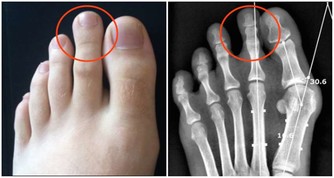

腳溝炎,是指腳指甲在受到外界的擦傷、刺傷、割傷後。因為沒有得到及時的處理,而受到局部的感染,細菌堆積,導致甲下發生膿腫,這是腳溝炎最主要的病因。此外,趾甲剪得太短或長期不剪趾甲、長期穿不合適的鞋子也會造成腳溝炎的發生。

(1)若趾甲有輕微損傷時,可以用碘酒進行消毒,用創可貼進行包紮,防止進一步感染。

(2)可外敷三黃散或者魚石脂軟膏,必要時可服用抗生素藥物。

(3)如果已經出現甲下化膿,應當到醫院去及時切開或將趾甲拔去,擠出膿液。